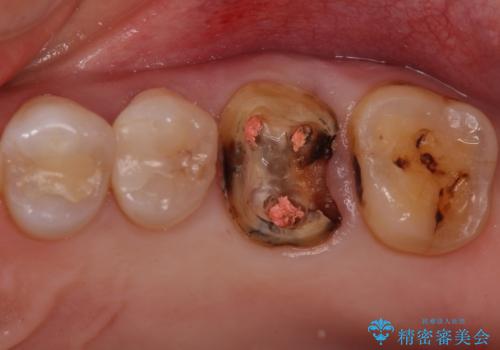

- 検査の結果被せ物の下に虫歯が確認された患者様です。

虫歯を取りきった後セラミッククラウンでの修復処置を行います。

被せ物の裏側の虫歯は被せ物を取らないと除去できません。

今回は過去に治療された部分をすべてやり直しました。